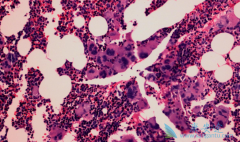

骨髓纤维化 (MF)是一种骨髓造血干细胞异常克隆所致的、以骨髓中出现网状纤维和胶原纤维为特征的血液恶性肿瘤,包括PMF,以及继发于PV和ET的PPV-MF和PET-MF。在芦可替尼出现以前,MF没有有效治疗药物,只能等待疾病进展进而对症处理。芦可替尼是一种强 ...